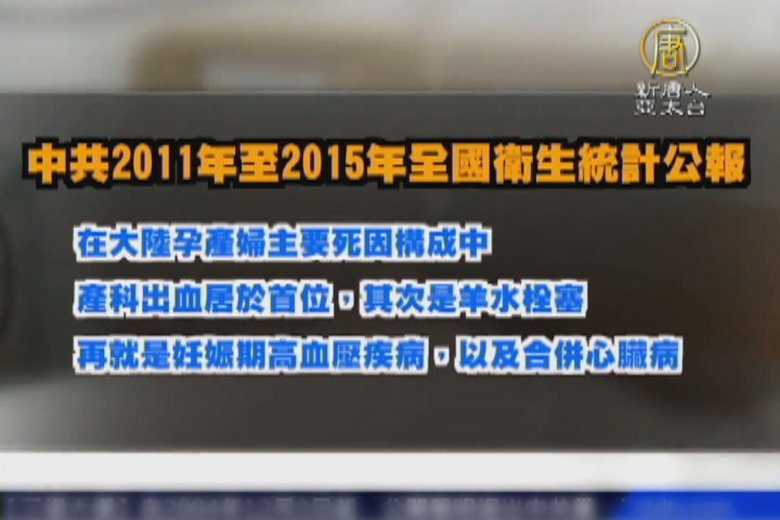

二孩政策惹的禍?大陸孕婦死亡率暴增

2016-10-28 11:42:12中國大陸今年一月起全面實施「二孩政策」,官方統計,今年上半年全國孕婦和產婦死亡率,比去年同期增加三成。有評論指出,孕產婦死亡率暴增,跟醫護人員和醫療資源投入不足有關。